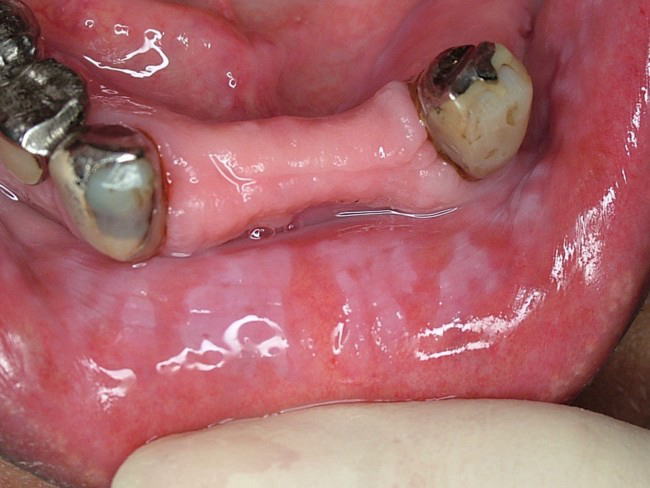

■ 白板症(ロイコプラキア) ■

頬粘膜をはじめ口唇、舌、歯肉、口腔底粘膜などに発現する”摩擦によって除去できない”白斑病変。下の写真は口唇に発現した白板症(同一写真)です。口腔粘膜疾患としては比較的頻度が高く、単発で生じることも、また写真のように広範囲に生じることもあります。表面は粗いもの、丘陵上のもの、乳頭状のもの、また境界が限局性のもの、びまん性のものなど様々な病態を示します。状態によっては前癌病変としての性格を持つものもあります。

疼痛などの自覚症状は少ないのが普通です。

治療は原因除去(不適合な補綴物の刺激によって生じたものなど)、切除、レーザー照射などがありますが、原因や病態によって多様です。

鑑別診断を要するものとしては、扁平苔癬やカンジダ症などがあります。